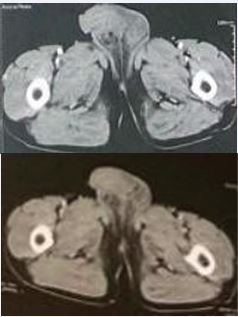

Given the atypical macroscopic appearance and the lesion’s slow progression, a thoracoabdominopelvic CT scan was performed. The scan showed diffuse scrotal edema centered on a 20 mm anterior inter-testicular abscess and revealed a micronodular and bronchial pattern in the lungs, suggestive of granulomatous disease, most likely tuberculosis. No secondary lymph node or visceral involvement was observed (Figure 2).

Figure 2 CT-Scan showing the scrotal mass.